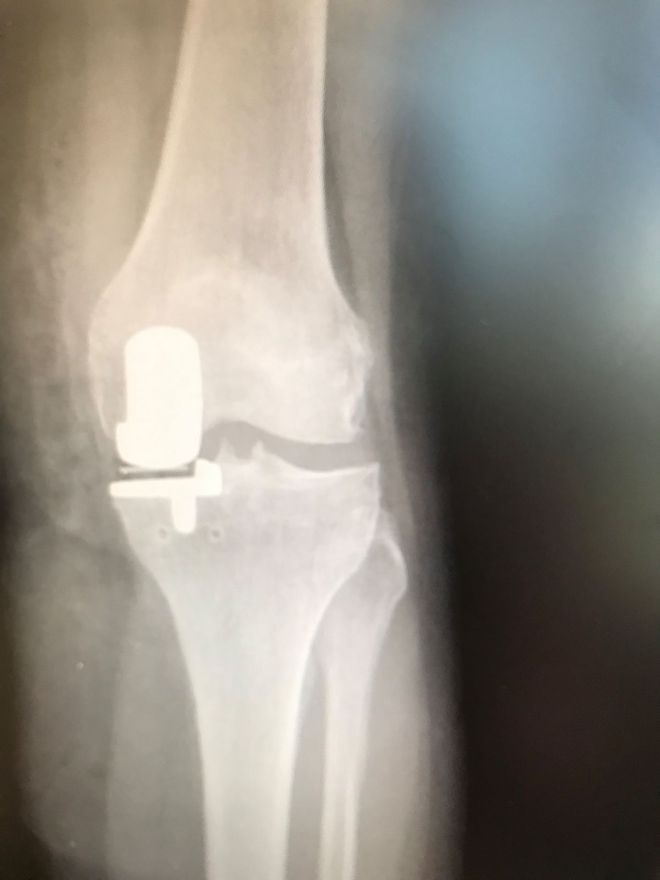

Ειδικότερα, η Μονοδιαμερισματική Αρθροπλαστική Γόνατος (ΜΑΓ) είναι μία καθιερωμένη θεραπευτική επιλογή για γόνατα που πάσχουν από αρθρίτιδα σε ένα μόνον τμήμα τους (εικ. 1) και αποτελείται από τρία μέρη: Από το μηριαίο τμήμα, το οποίο κατασκευάζεται από μέταλλο, από μια μεταλλική βάση, η οποία τοποθετείται πάνω στην κνήμη, και ανάμεσα τους υπάρχει ένα πλαστικό, κινούμενο τμήμα (πολυαιθυλένιο) (εικ. 2).

Μέσω μίας μικρή τομής στην πρόσθια επιφάνεια του γόνατος, αποκαλύπτεται η άρθρωση. Ο χειρουργός θα αφαιρέσει τμήμα του μηνίσκου που είναι κατεστραμμένος και τα τμήματα της αρθρώσεως που πάσχουν θα επικαλυφθούν με δυο μικρές προθέσεις, μία στο μηριαίο οστούν και μία στην κνήμη.

Το πλαστικό εξάρτημα το οποίο βρίσκεται ανάμεσα στις δύο μεταλλικές αυτές προθέσεις είναι κινούμενο και υποκαθιστά τον κατεστραμμένο μηνίσκο που αφαιρέθηκε. Τα μεταλλικά υλικά μπορούν να τοποθετηθούν στο οστούν με ή χωρίς τη χρήση τσιμέντου, ανάλογα την περίπτωση.